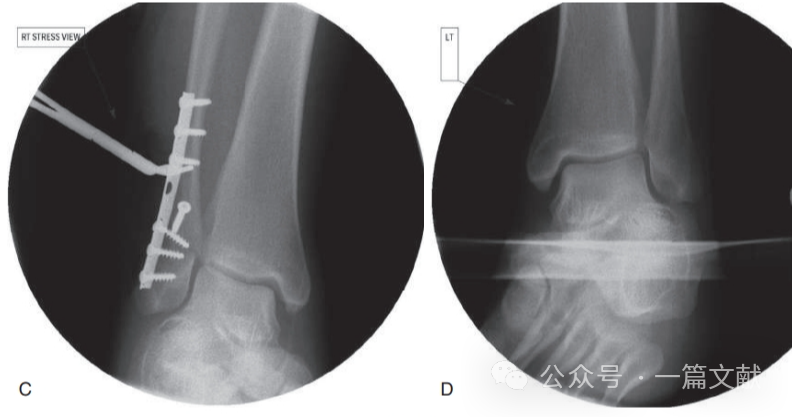

3,复位下胫腓时,复位钳夹持方向出现偏差,或螺钉置入方向有误,造成腓骨一定程度的旋转,未解剖复位。如下图:理想的夹持复位点是腓骨远端外侧凸起与内踝前部最高点,来实现踝关节的轴向加压。螺钉置入时同理。建议前方直视下观察腓骨远端与胫骨切迹的关系。

4,当下胫腓联合部骨折粉碎时,此时钳夹复位或拧入螺钉时,容易形成过度复位。如下图: